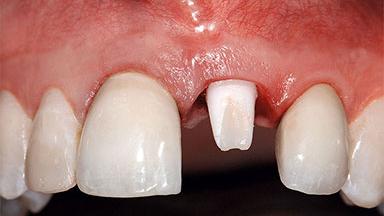

A healthy 37-year-old female patient was referred for a consultation on the replacement of missing tooth 21 with an implant-supported restoration. She stated that several years previously the tooth had been traumatically avulsed following a motor vehicle accident. The tooth was replaced with a three-unit fixed partial denture (FPD) immediately afterwards. Over time, she became disillusioned with the FPD and looked for a different option, including orthodontic therapy. She presented still in her orthodontic appliances, with the pontic sectioned free from the FPD but attached to the archwire. Her orthodontist felt that orthodontic treatment had been successfully completed, but nevertheless referred her before removing the appliances in case adjustments were necessary.

Placement Protocol Early or late implant placement